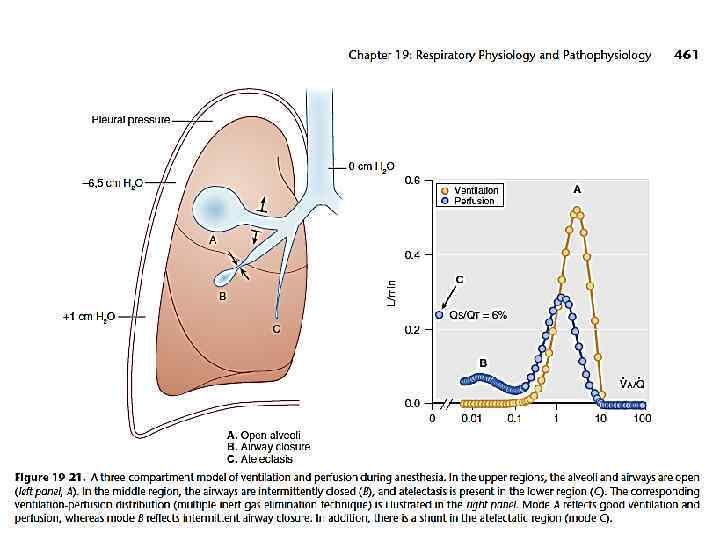

Факторы риска Оперативное вмешательство Ателектазы

Факторы риска Оперативное вмешательство Ателектазы

Интубация и наркоз как показание для рекрутмента

Интубация и наркоз как показание для рекрутмента

Chepter -19 Respiratory Physiology Göran Hedenstierna

Chepter -19 Respiratory Physiology Göran Hedenstierna